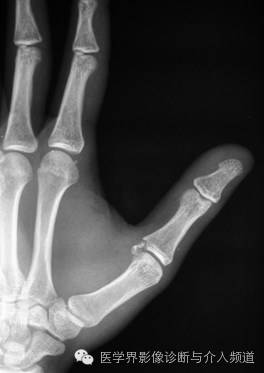

5、Boxer’s 骨折

第5掌骨头横形骨折。远折端向掌侧移位,向背侧成角。